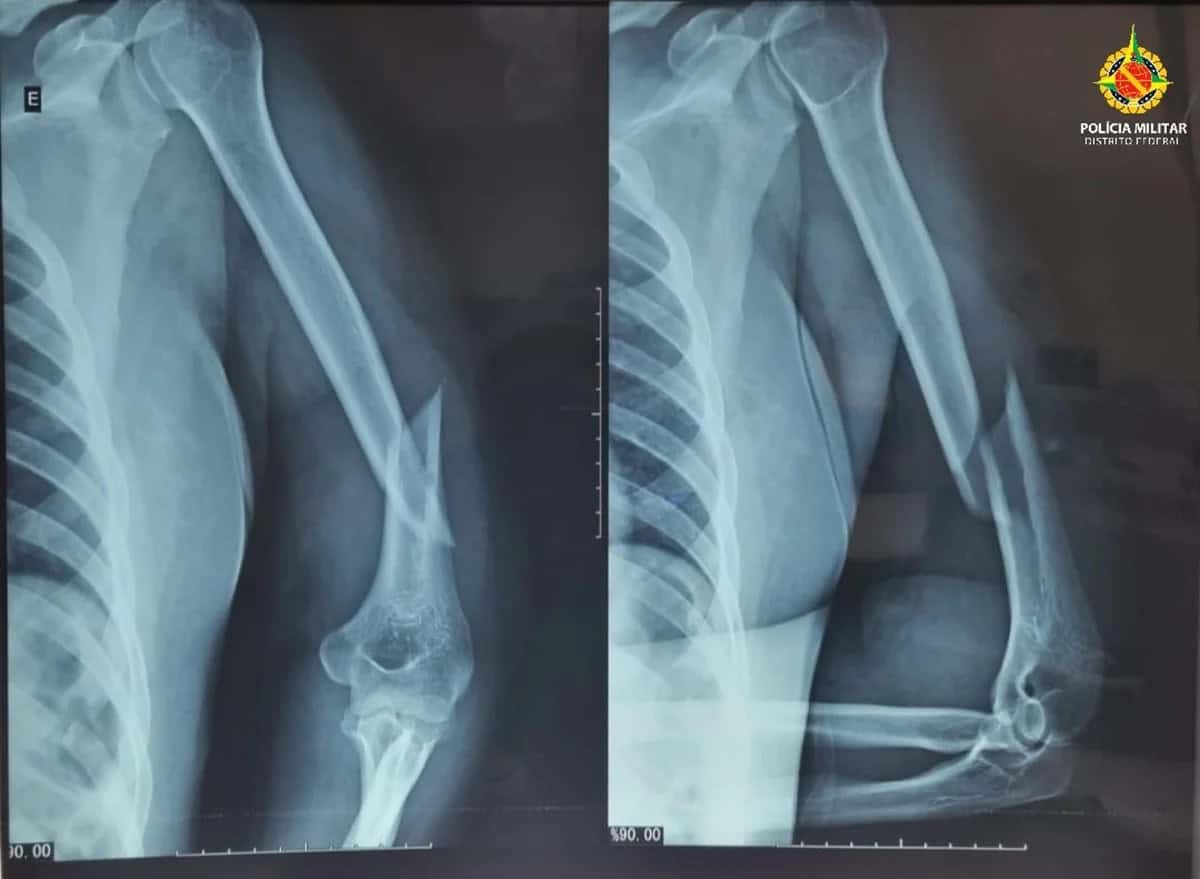

Segundo a Polícia Militar do DF (PMDF), uma equipe foi acionada para atender uma ocorrência de violência doméstica e, no local, constatou que a vítima, de 41 anos, apresentava hematomas no rosto, inchaço ao redor dos olhos, sangramento pelos ouvidos, fratura no úmero esquerdo e luxação no ombro esquerdo.

Uma equipe médica do Serviço de Atendimento Móvel de Urgência (Samu) informou aos policiais que o quadro clínico era sugestivo de traumatismo cranioencefálico.

A mulher relatou que vinha sendo agredida desde a meia-noite pelo companheiro e que foi uma vizinha que acionou a PMDF, após ouvir os pedidos de socorro. A vítima foi socorrida e encaminhada ao Hospital Regional de Taguatinga (HRT), onde permanece internada, aguardando procedimento cirúrgico.